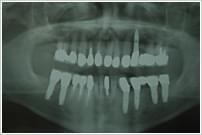

インプラントの治療例 (61歳)

咀嚼障害のご相談をいただきました。

全顎にわたる重度の歯周炎、動揺、排膿。

上下顎の歯周治療を行い、下顎臼歯インプラントによる全顎補綴。